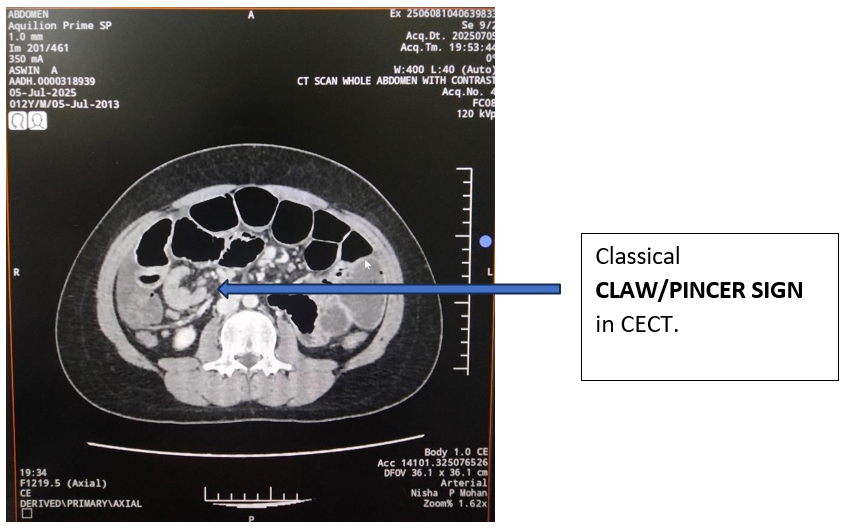

- ileocolic intussusception with telescoping of distal ileal loops into the colon at the ileocecal junction and proximal small bowel obstruction.

- Linear fat density lesion (-90 HU) within the telescoped segment, likely representing a lipoma, which may serve as a lead point.

Picture 1,Picture 2